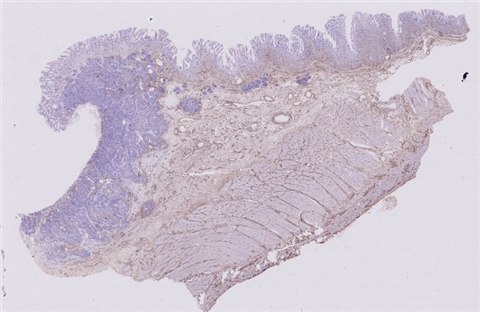

患者详情: 患者4月前开始出现上腹胀痛不适,进食后加重,伴梗咽感,不伴恶心呕吐、腹泻便秘、畏寒发热等不适,因症状持续遂当地医院就诊,行电子胃镜检查示:贲门-胃体CA? 胃镜:贲门、胃底见一大小约2.0*1.5厘米不规则溃疡面,覆污苔,取检质脆易出血,粘液湖清。 CT:贲门胃底区壁不规则增厚并软组织肿块影,边界不清,突向腔外,邻近胃周脂肪毛糙,增强呈明显不均匀、持续性强化,胃周结构层次毛糙,胃周见稍大淋巴结,呈中等欠均匀强化。贲门胃底区增厚并肿块,胃周浸润,请结合胃镜检查。 肿瘤标志物:CEA、CA199、CA125均正常

大体所见: 全胃切除标本:大弯长24cm,小弯长15cm,附网膜14*11.5*5cm,距贲门切缘2cm处于小弯侧见4.5*4.5*2.5cm溃疡性肿物,切面灰白色,实性,质硬,肉眼侵及全层。

医院: 南昌大学第二附属医院